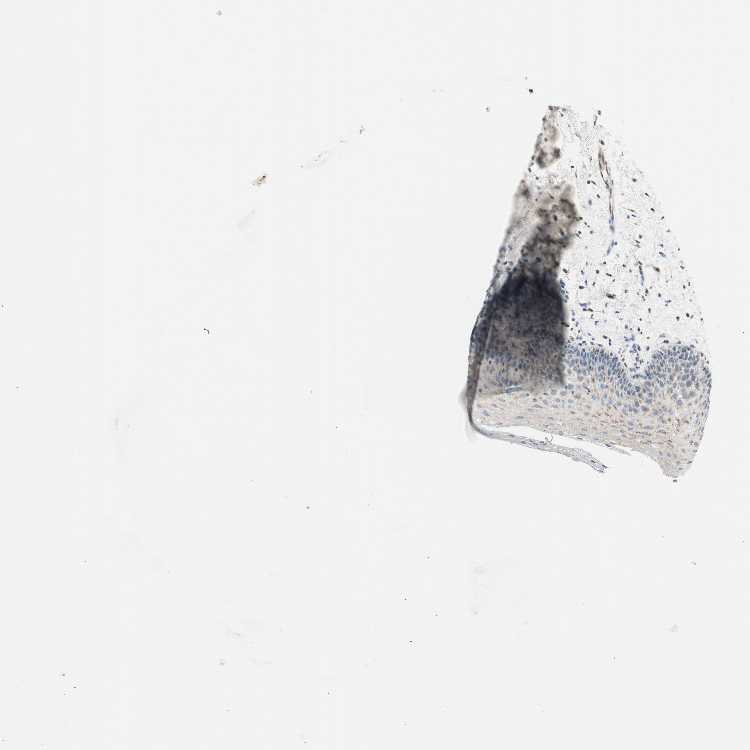

TISSUE PRIMARY DATA ORAL MUCOSA Show tissue menu

ORAL MUCOSA - Antibody stainingi

Antibody staining in the annotated cell types in the current human tissue is reported as not detected, low, medium, or high, based on conventional immunohistochemistry profiling in selected tissues. This score is based on the combination of the staining intensity and fraction of stained cells.

Each image is clickable and will lead to virtual microscopy that enables deeper exploration of all samples and also displays staining intensity scores, fraction scores and subcellular localization as well as patient and tissue information for each sample.

Antibody HPA008729

Squamous epithelial cells Medium